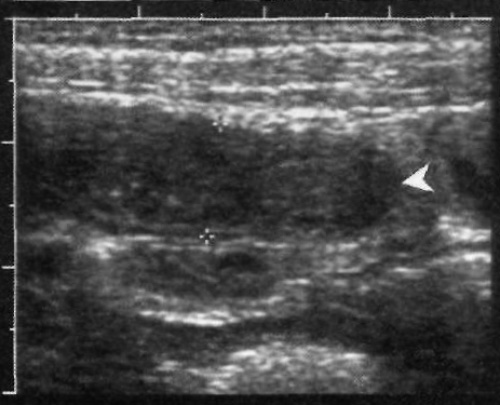

В норме ультразвуковая картина аппендикса демонстрирует трубчатую структуру, которая сжимается и имеет слепое окончание. Типичная внутренняя гиперэхогенная линия окружена гипоэхогенной внешней зоной – эти образования соответствуют подслизистому слою и собственной мышечной оболочке (фото 1). Поскольку червеобразный отросток в большинстве случаев извитой или изогнутый, иногда его невозможно полностью вывести на одном изображении.

Фото 1. Червеобразный отросток в норме. Продольное ультразвуковое изображение здорового аппендикса: стрелками обозначен внутренний гиперэхогенный слой слизистой оболочки, которую окружает гипоэхогенная собственная мышечная оболочка. Указателями отмечена вогнутая передняя стенка при ее сдавлении